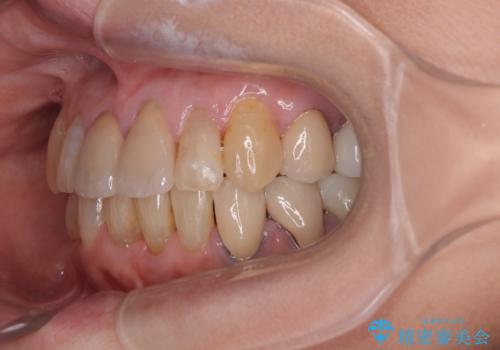

- 長年気にしていた捻れた前歯が欠けたとのことで来院された患者様です。

矯正治療に抵抗があったそうですが、前歯が欠けたことをきっかけに、矯正治療で歯列を整えた上で、セラミッククラウン治療を行う決心が付いたとのことでした。

デコボコが強いため、ブリッジや残根となっている部分のスペースを利用して歯列を整え、変色や欠けている歯をオールセラミッククラウンによる補綴治療を行うこととしました。

歯肉移植などによる前歯部の歯肉ライン改善を提案しましたが、口を開けたときにほとんど見えないので気にならないとのことで、特に処置を行うことなく補綴治療を行いました。